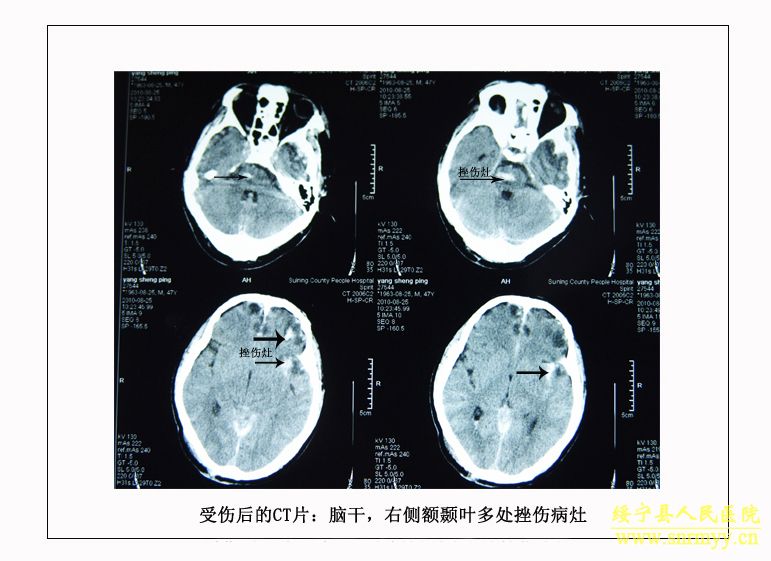

经检查:当时病人体温36.5℃、脉搏105次/分钟、呼吸25次/分钟、血压152/98mmhg,呈昏迷状,头面部、右手、左下肢均不同程度受伤,双侧瞳孔不等大,光反射消失;同时右手臂和左大腿均有骨折。GCS评分:仅4分,根据评分标准(轻度颅脑损伤为12—15分、中度为8—12分、重度为5—8分、极重度为3—5分)该病人属于极重度颅脑损伤。CT检查结果为脑干挫裂伤、双侧额叶、左颞叶、右顶叶脑挫裂伤、左侧颞部硬膜外、下血肿,左顶硬膜下血肿,蛛网膜下腔出血,脑室内积血,左侧额部下积液,左眼框内侧壁,枕骨骨折。X光片显示右桡骨粉碎性骨折,左股骨干骨折。诊断为:1、极重度颅脑损伤:(1)脑干挫裂伤。(2)双侧额叶、左颞叶、右顶叶脑挫裂伤。(3)右颞部硬膜外血肿。(4)外伤性蛛网膜下腔出血。(5)枕骨骨折。(6)头皮多处挫裂伤。2、右桡骨粉碎性骨折。3、左股骨干骨折。临床上如此严重的脑损伤死亡率极高,再加上合并多处骨折创伤,病人危在旦夕。